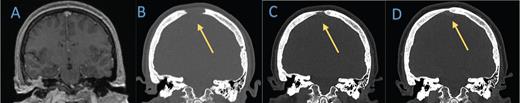

Axial T2 sequence of A) a brain MRI from 2019 demonstrates diffuse opacification of right mastoid air cells and lytic changes of the right temporal bone. A B) head computed tomography (CT) scan obtained in February 2021 shows erosion of the bony septate and partial opacification of the mastoid air cells. C) Nine months later, CT of the head reveals an interval decrease in the amount of fluid collection in the mastoid portion of temporal bone and reactive sclerotic changes. D) The most recent head CT in July 2022 shows stable changes.